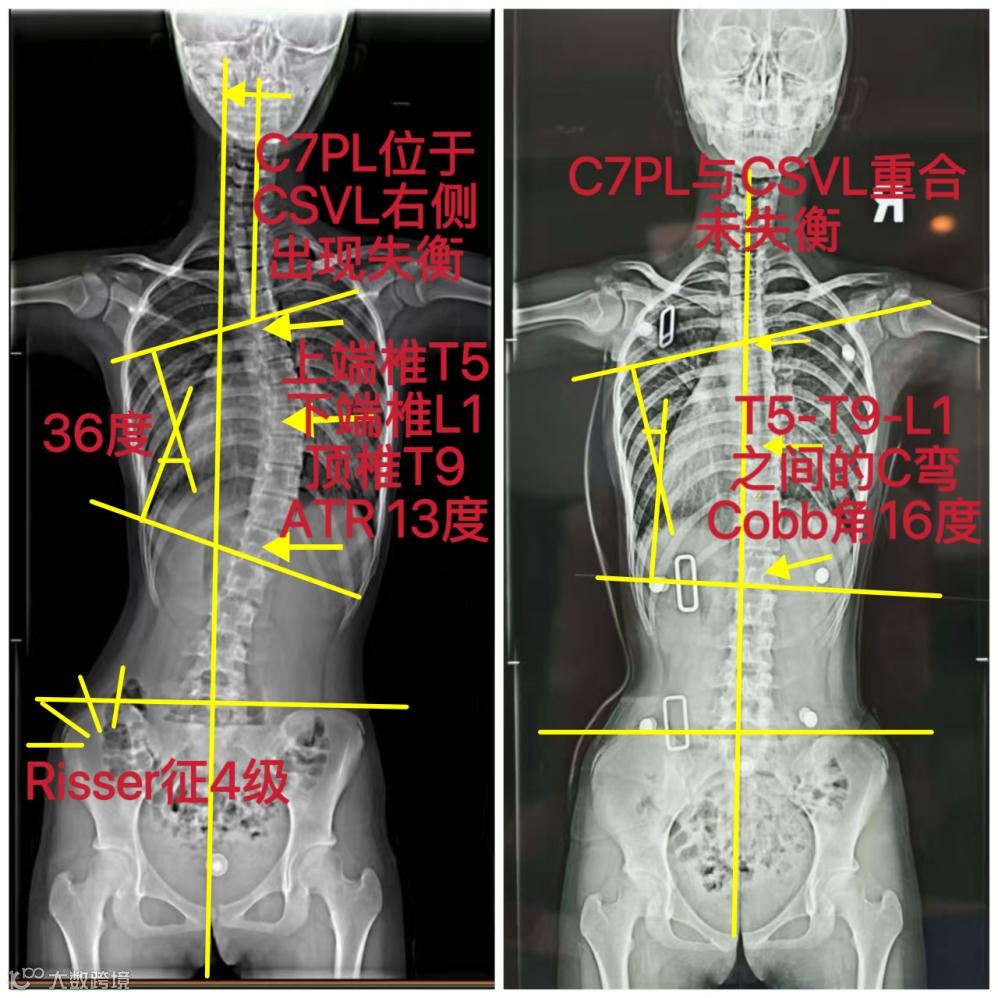

范同学,女,13岁,因参加为期一周的学校军训强化训练后,出现持续性腰背部酸痛,家长遂带其至医院骨科就诊,经影像学检查与临床评估,确诊为青少年特发性脊柱侧弯,具体检查结果如下:

X线检查:胸腰段脊柱呈C型侧弯

Cobb角为36度

ATR角为13度

脊柱柔韧性中等

Risser征达到四级,表明骨骼成熟度已较高。

矫正前

X线检查:胸腰段C型侧弯

Cobb角为36度(中度)

伴随腰背部酸痛症状

Risser征达到四级

矫正后

X线检查:胸腰段C型侧弯形态保持稳定

Cobb角为16度(轻度)

ATR角较之前显著改善

腰背部酸痛症状基本缓解

Risser征仍为4级